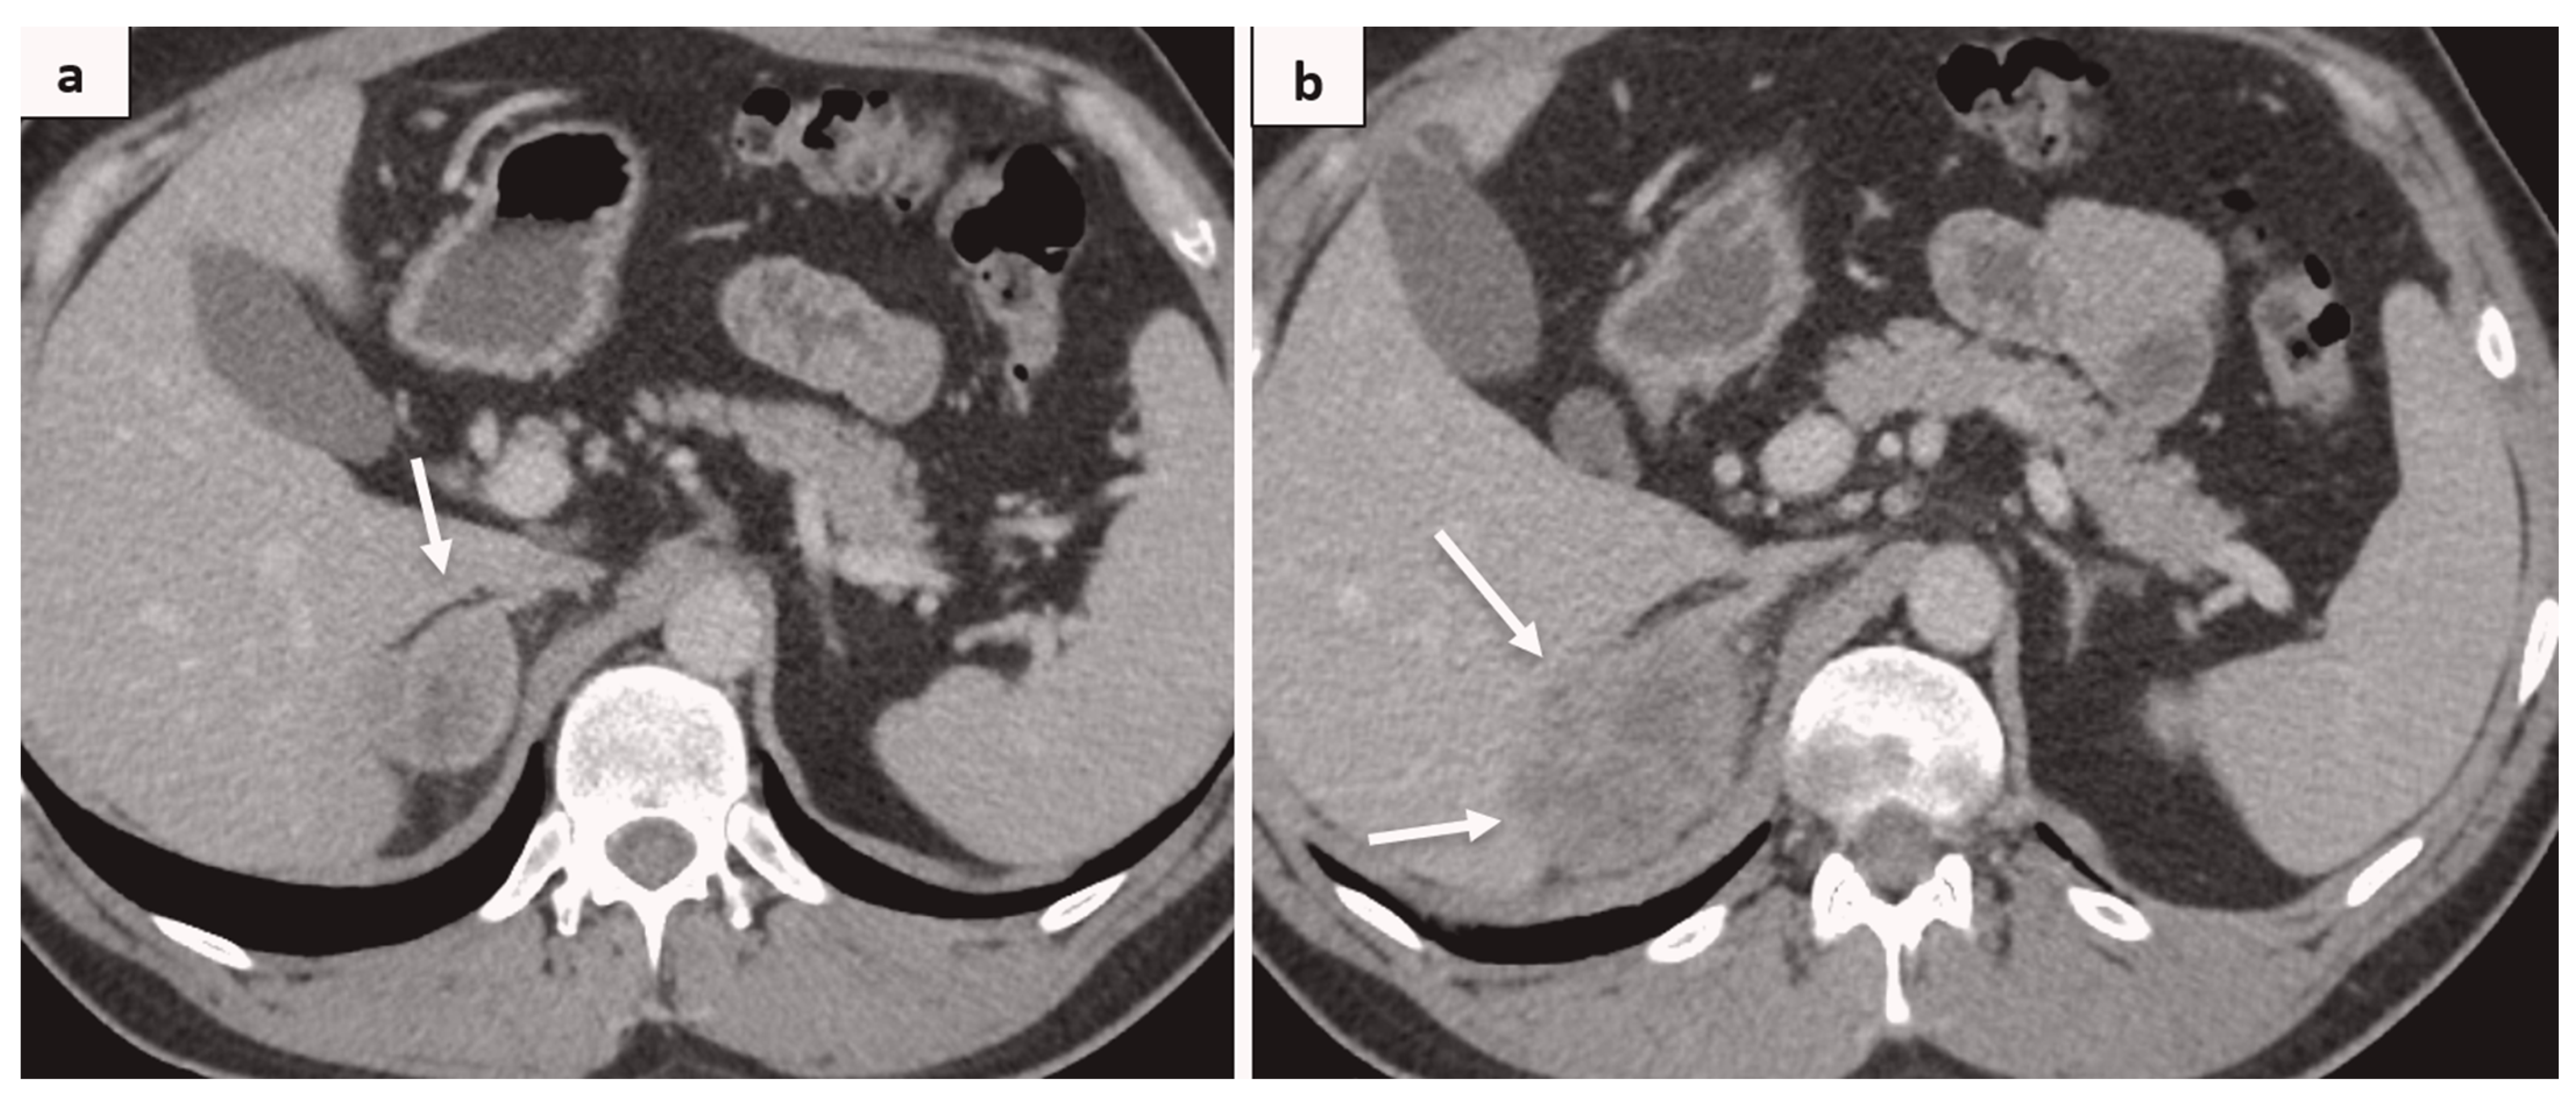

2. Case Report